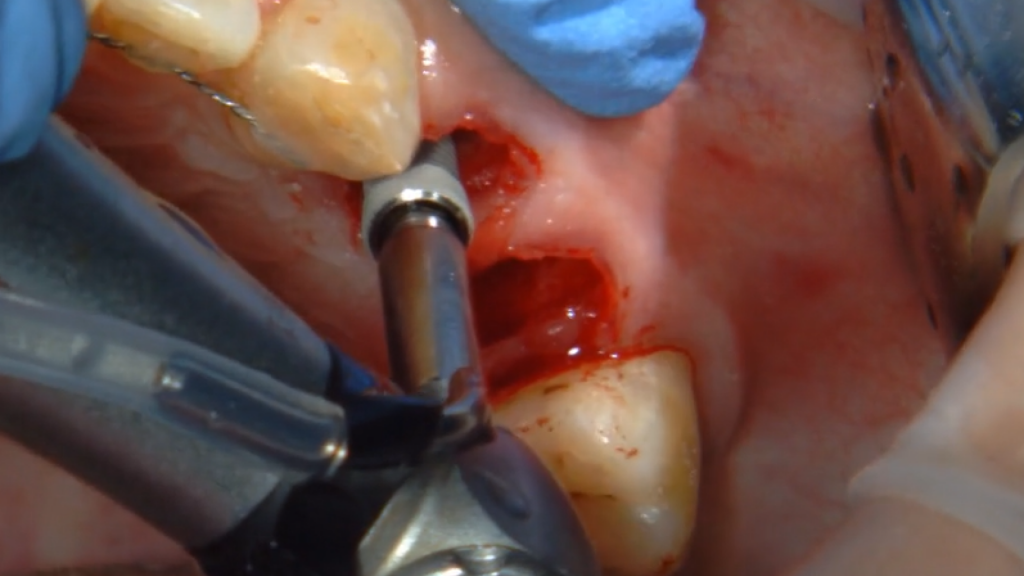

Одномоментная имплантация Impro с установкой временного абатмента

Описание клинического случая:

• Атравматичное удаление зуба 2.4, 2.5

• Одномоментная дентальная имплантация IMPRO

• Использование фибриновой мембраны Clot-PRF

• Установка временного абатмента IMPRO

• Изготовление индивидуального формирователя десны

Клинический случай Узденовой Зульфы Альбертовны